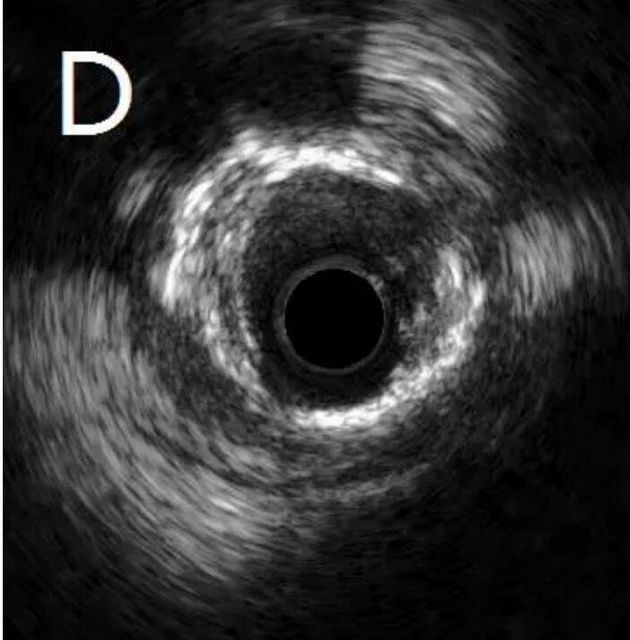

患者为77岁女性,因冠心病进行冠状动脉介入治疗,造影发现冠状动脉前降支不仅闭塞(图A),而且伴有钙化。通过不懈的努力,将闭塞的血管打开,但钙化处球囊无法将病变充分扩张(图B),意味着无法通过植入支架来维持血管管腔。于是采用血管内超声对病变处进行检测,显示病变处存在严重的360度环形钙化(图C、D)。